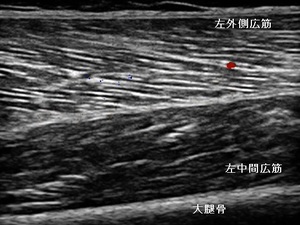

右もも外側部 超音波長軸像 左同部 超音波長軸像

当接骨院での初診時は、深く膝を曲げることができず、患部の圧痛や熱感が著明でした。超音波観察を

行ったところ、右大腿四頭筋の外側広筋と中間広筋の損傷部に血流が増勢し、内出血と浮腫が認められました

(左上画像の丸の囲み)。